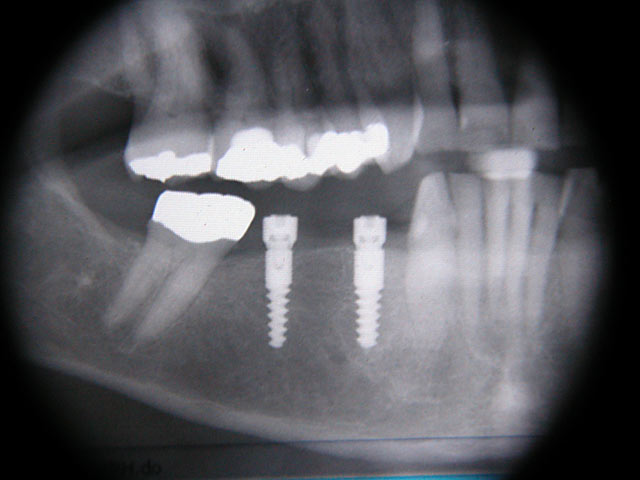

Implantation mit externem Sinuslift: